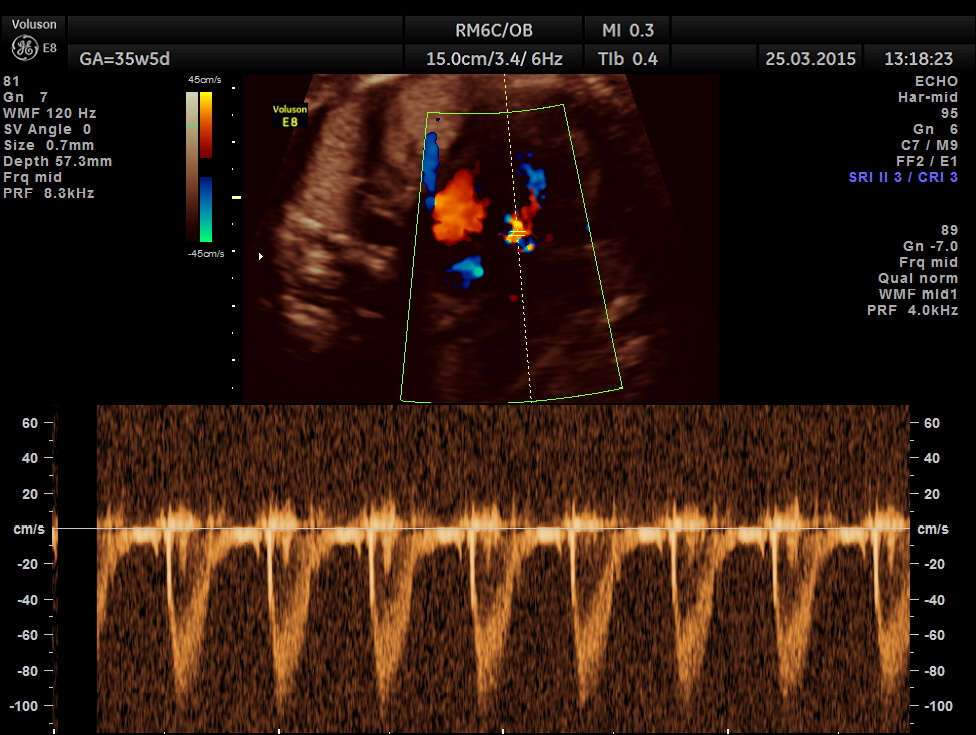

Tricuspid doppler flow.